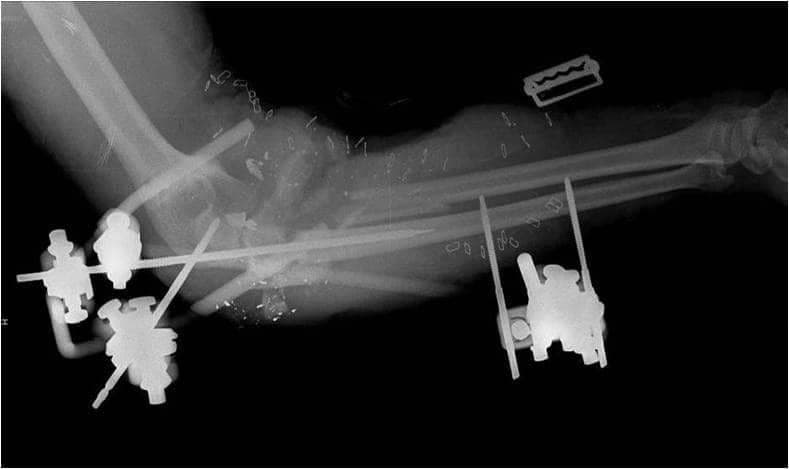

2. Уникайте встановлення штифта занадто близько до місця перелому (штифти всередині самого перелому зменшать здатність зовнішнього фіксатора підтримувати стабільність перелому) (зобр. 2 і зобр. 3. Рентгенологічний знімок цієї гомілки у прямій проекції передбачає адекватне розміщення зовнішнього фіксатора, проте на бічному знімку видно, що проксимальний штифт дистальної групи штифтів знаходиться всередині перелому).

Зобр. 2

Зобр. 3